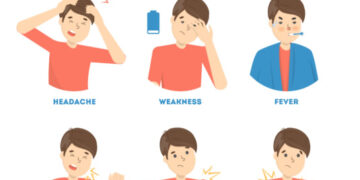

Read moreডা. মোহাম্মদ আজিজুর রহমান ,বক্ষব্যাধি ও মেডিসিন বিশেষজ্ঞ চারদিকে অনেকেরই জ্বর, কাশি ও গলাব্যথার মতো উপসর্গ দেখা দিচ্ছে। করোনাভাইরাসের সংক্রমণের...